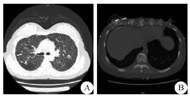

女性,25岁,因"发热20余天,突发右侧肢体无力4 d"于2014年7月9日由首都医科大学附属北京朝阳医院神经内科收治入院。患者入院前20 d受凉后出现发热,最高体温38.8 ℃,伴咳嗽,咳嗽时伴头痛,给予口服感冒药略有好转;入院4 d前安静状态下突发右侧肢体无力,行走轻度乏力,右手持物不稳,无言语不利,头部CT提示"左侧脑桥低密度灶"。近1月体质量下降5 kg。既往体健,父亲19岁时患有结核性胸膜炎病史。入院体检:血压118/55 mmHg(1 mmHg=0.133 kPa)。化验检查:(1)血常规、凝血功能、肝炎、自身抗体、体液免疫、髓过氧化物酶、蛋白酶、自身免疫缺陷病毒、梅毒、肿瘤标记物、甲状腺功能等均正常;(2)生化:C反应蛋白1.10 mg/dL(↑),动态红细胞沉降率25 mm/h(↑),总胆固醇3.06 mmol/L(↓),高密度脂蛋白胆固醇0.77 mmol/L(↓),低密度脂蛋白胆固醇1.40 mmol/L(↓),甘油三脂2.95 mmol/L(↑),余生化全项大致正常;(3)脑脊液:初压120 mmH2O(1 mmH2O=0.0098 kPa),无色透明,潘氏试验阴性,白细胞53/nL,红细胞1/nL,单核73.6%,多核26.4%,糖1.9 mmol/L(↓),氯化物121.8 mmol/L,蛋白46 mg/dL(↑),腺苷脱氨酶3 U/L,脑脊液病原学阴性;(4)血结核杆菌抗体试验阳性,血肺炎支原体抗体IgM阳性,血肺炎衣原体抗体IgM阳性;血混合淋巴细胞培养+干扰素检测A:>1000 SFCs/106,血混合淋巴细胞培养+干扰素检测B:164 SFCs/106,血真菌-β-D葡萄糖<10 pg/mL,血降钙素原0.11 ng/mL。影像学检查:(1)头颅MRI :左侧桥脑呈现异常高信号改变,增强序列可见明显强化病灶(图1)。(2)头部MRA和颈部CTA:未见明显异常。(3)胸部CT:双肺粟粒样结节及沿支气管血管束分布稍大结节,考虑结核血行播散合并气道播散;T10椎体骨质局限性低密度灶,考虑胸椎结核(图2)。(4)支气管镜检查:左肺尖后端支气管镜活检提示支气管黏膜慢性炎症;石蜡切片提示典型分支杆菌阴性,结核杆菌临界阳性。

A:胸部CT示双肺粟粒样结节;B:胸部CT示胸10椎体结核